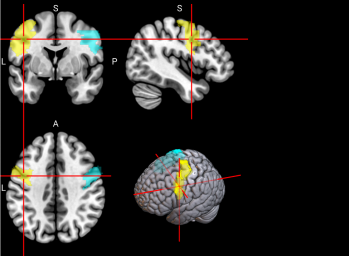

71,

72

L & R Precuneus (PCUN)

The precuneus is involved in recollection and memory, perception, episodic memory, and other cognitive processes [67].

/word/media/image16.png/word/media/image16.png